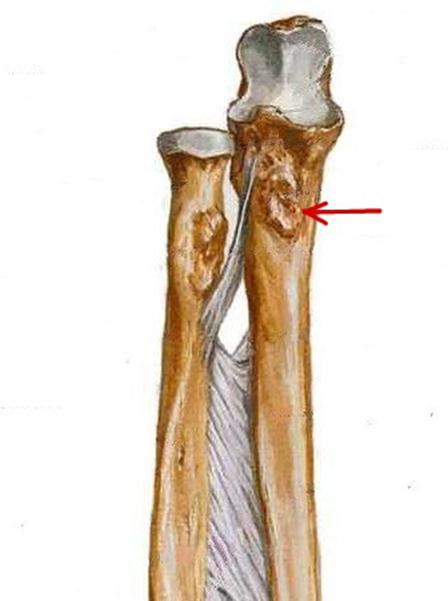

S: Стрелка указывает на...

+:tuberositas ulnae